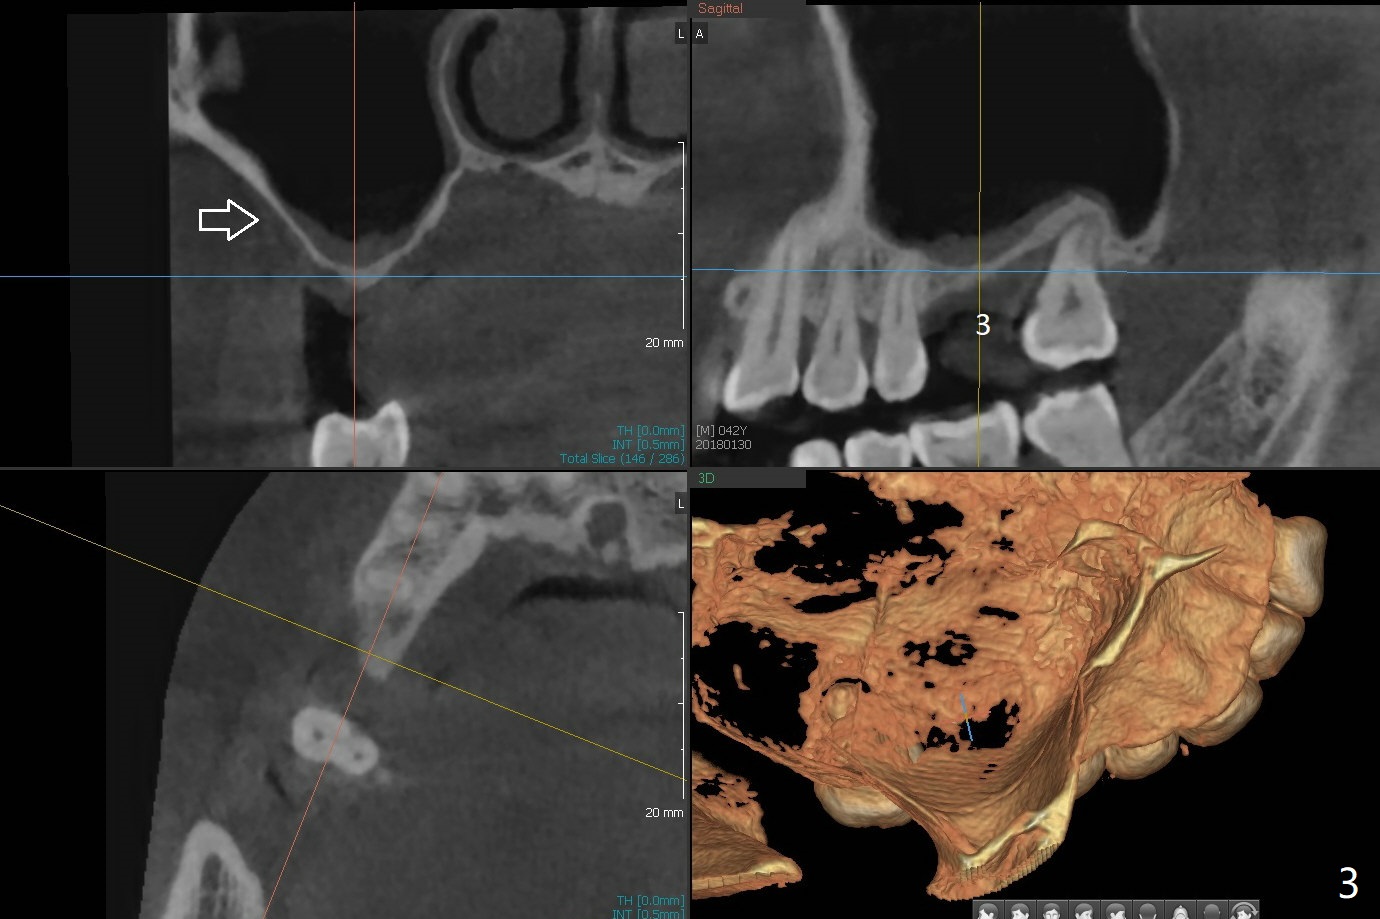

A 43-year-old man has ~ 2 mm bone at #3 (Fig.1). To reduce sinus membrane perforation and abutment screw loosening, a shorter, but larger Magicore will be used (5x7(3)) if an implant is to be placed at the same time of bone graft. Since the crestal bone is loose (Fig.2 *), internal sinus lift is feasible with Magic Sinus Lifter. Flap surgery will make it easy to place bone graft to increase crestal bone height as well as bone volume surrounding the neighboring teeth. A 6-month membrane will be used for guided bone regeneration (GBR). A spacer will be placed to keep the space and replace a flipper the patient is wearing now. The spacer is favorable for wound healing. PRF membranes will be prepared (x3). External sinus lift seems to be safer (Fig.3 arrow).